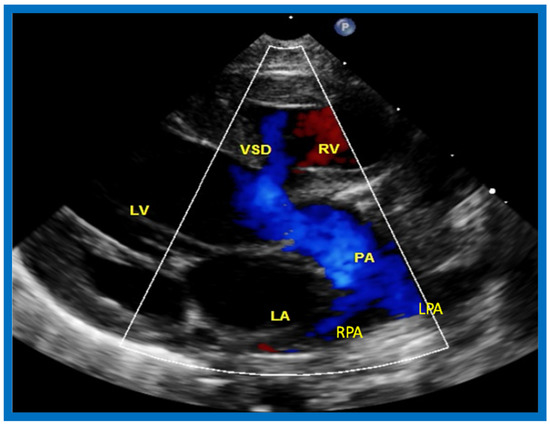

The relationship of the great arteries is examined next in order to classify them into various types [41]. The relationship of the great arteries is established by following the vessels arising from the ventricles until pulmonary bifurcation or aortic arch. In Type I patients with normally related great arteries, the aorta arises from the LV (Figure 20), while in Type II patients with transposition of the great arteries, the PA arises from the LV (Figure 21 and Figure 22). In Type III patients, it may be little more difficult to assign the great artery relationship, and sometimes angiography is needed. In type IV with truncus arteriosus, the limited data [22] suggest that this can be done by echocardiography (Figure 23 and Figure 24).

Figure 22.

Selected video frame from precordial long axis view with color flow mapping of another neonate with tricuspid atresia and transposition of the great arteries illustrates the left atrium (LA), left ventricle (LV), a small right ventricle (RV) and a moderate sized ventricular septal defect (VSD). The vessel coming off of the LV bifurcates into left (LPA) and right (RPA) pulmonary arteries. Reproduced from Rao P.S. [39].